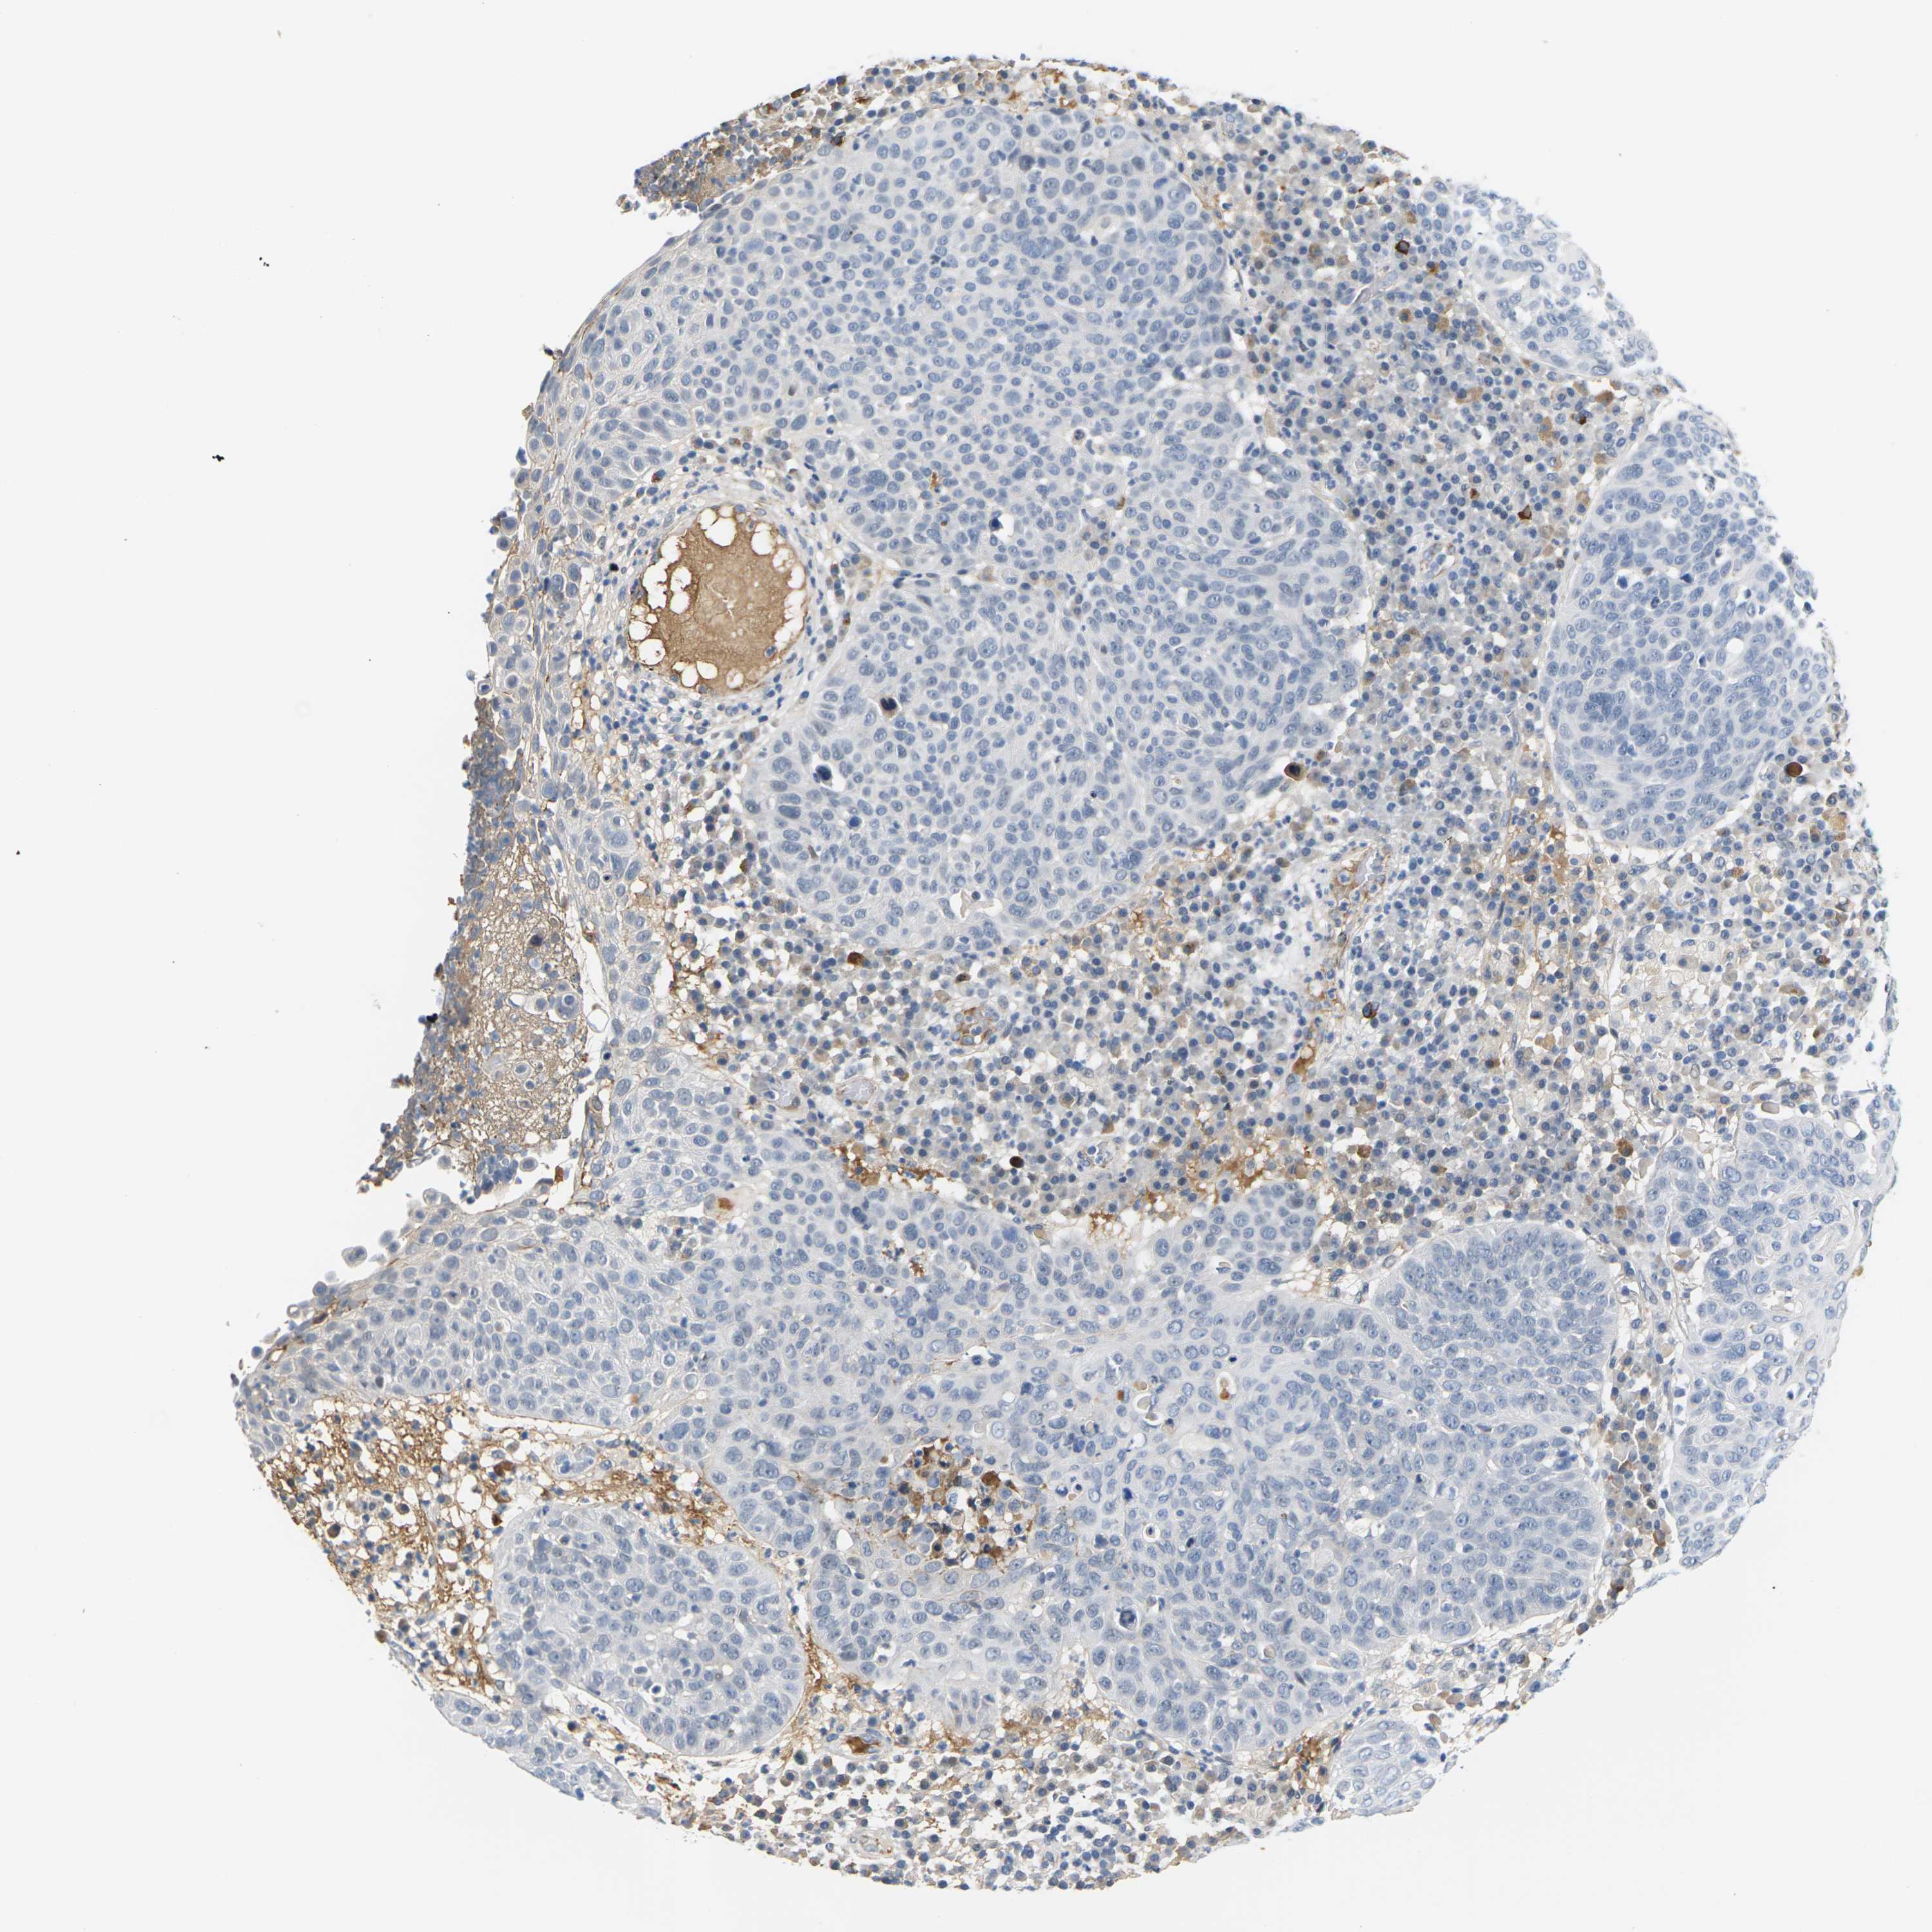

SKIN CANCER - Protein expressioni

A mouse-over function shows sample information and annotation data. Click on an image to view it in a full screen mode. Samples can be filtered based on level of antibody staining by selecting one or several of the following categories: high, medium, low and not detected. The assay and annotation is described here.

Antibody stainingi

Antibody staining in the annotated cell types in the current human tissue is reported as not detected, low, medium, or high, based on conventional immunohistochemistry profiling in selected tissues. This score is based on the combination of the staining intensity and fraction of stained cells.

Each image is clickable and will lead to virtual microscopy that enables deeper exploration of all samples and also displays staining intensity scores, fraction scores and subcellular localization as well as patient and tissue information for each sample.

Antibody HPA014314

Squamous cell carcinoma in situ, NOS